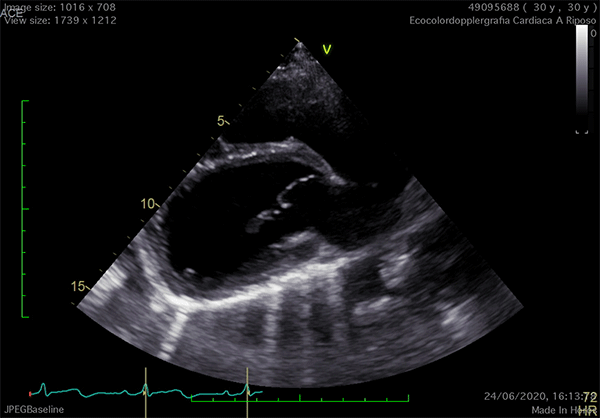

Case

https://academic.oup.com/ehjcimaging/article/12/11/E43/2396998